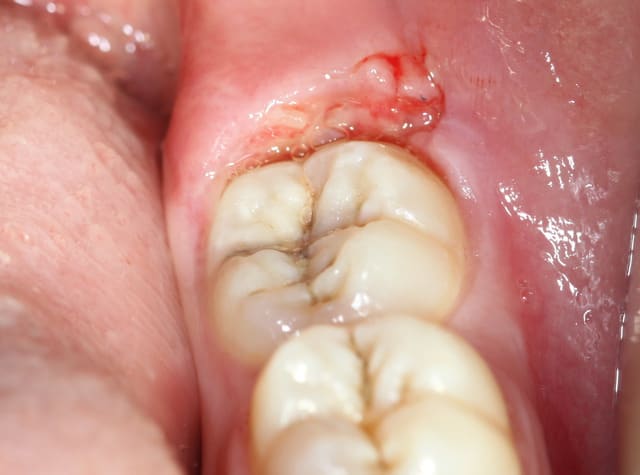

voila finalement on a opter pour la conservation de la dent...

Décapuchonné à la lame froide saignement modéré (infiltration d’anesthésie adrénalinée tout autours de la couronne... Un point de suture dix jours après compo. conseils d’hygiène.

la patiente est contente d'avoir conserver sa dent...